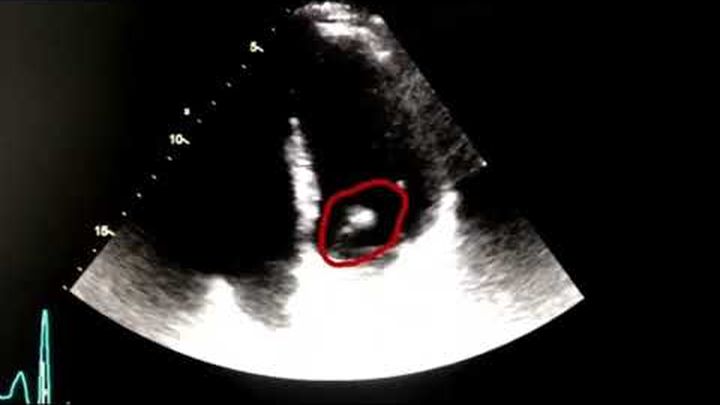

En août 2018, ma vie a basculé. J’ai été transporté d’urgence à l’hôpital avec un pronostic vital engagé. On m’a diagnostiqué une endocardite septique causée par un staphylocoque doré, une infection rare et extrêmement grave qui attaque le cœur. Grâce à des traitements lourds et trois ans de lutte acharnée, j’ai survécu. Mais cette épreuve a bouleversé ma vie.